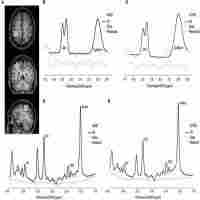

| Abstract | Background: In this article we provide an overview of the use of the functional magnetic resonance imaging (fMRI) and MR spectroscopy (MRS) in studies of autism spectrum disorders (ASD). We moreover provide preliminary data using these measures in cases of children with ASD and healthy controls. A hypothesis was that ASD children would show aberrant brain activation in the prefrontal and parietal cortex in an oddball stimulus situation, with predictable and unpredictable deviant tone stimuli, as an index of resistance to change in the ASD children. We also hypothesized that glutamate and GABA metabolite levels would differ between the two groups. Methods: fMRI images were acquired from a GE Signa HDx 3T MR scanner, as were the MRS data. Behavioral data were acquired as response accuracy to the deviant tone stimulus. The tone stimuli were presented in a standard fMRI ON-OFF box-car paradigim. Results: The fMRI results showed reduced brain activation in the ASD cases compared to the controls, preferably in the inferior and superior frontal gyrus, posterior temporal lobe, and superior and inferior parietal lobule. These areas make up an effort mode network (EMN), being activated in response to cognitive effort. The MRS results also showed differences between the groups. Discussion: The results are discussed in a theoretical framework of resistance to unexpected changes in the environment in ASD children, and how this could have a neurobiological underpinning. The results are also discussed in relation to the brain-gut link, and the possibility that ASD may have a microbial link. A limitation with the study is the few cases reported and the preliminary quality of the results. |